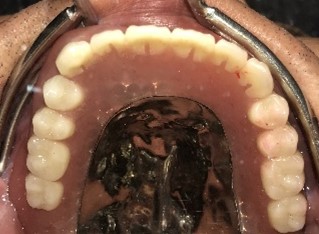

男性Iさん 50代(マグネット式入れ歯)

歯周病が進行し深刻な状態でした。保存することができない歯が上4本、下3本ありましたので、抜歯し、残った歯上4本、下7本の歯周病治療を徹底的にし、それらの歯を活用し上下マグネット式総入れ歯を入れました。

Before

赤丸は抜歯しました。上4本、下3本

After

【義歯を装着したところ】

【義歯を外したところ】

【マグネット式総入れ歯】

上顎

下顎